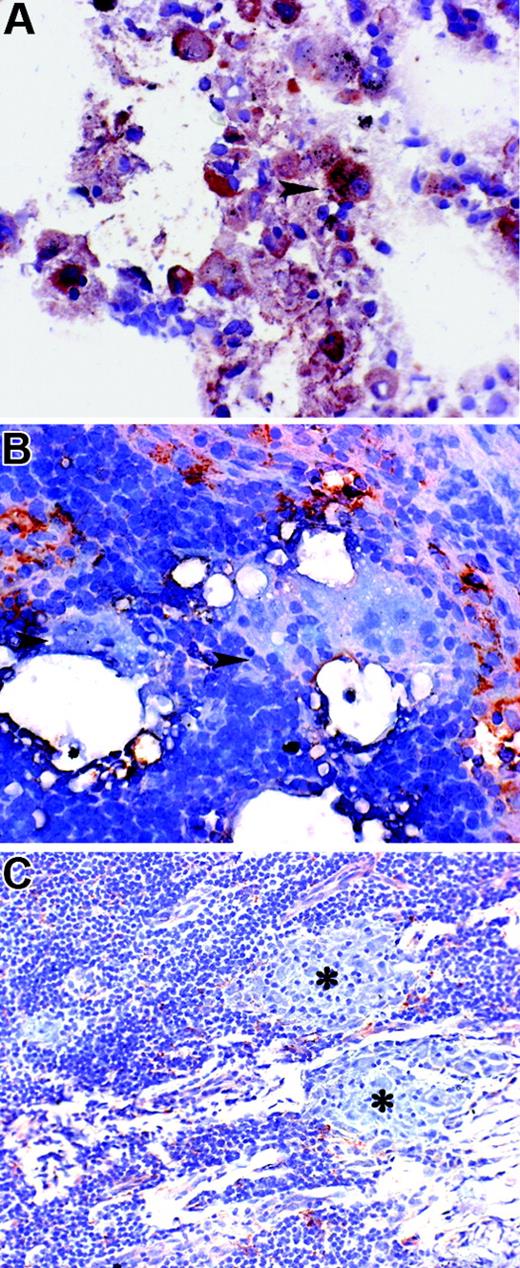

PTPγ expression was also investigated in tissue macrophages in the normal lung or was recruited at the site of inflammation. Alveolar macrophages appeared to strongly express PTPγ in their cytoplasm (Figure 6A); in contrast, PTPγ expression was not observed in multinucleated cells that accumulated at the site of inflammation in a patient with lymphadenitis caused by foreign body reaction (Figure 6B). In mycobacteria-induced lymphadenitis, granuloma lesions are mostly composed by a collection of specialized monocyte-derived macrophages called epithelioid cells admixed to a variable amount of T-lymphocytes. PTPγ expression was completely absent in all the cells that participated in the granuloma reaction, including epithelioid cells (Figure 6C). These data confirmed that the lack of PTPγ expression we observed in in vitro–differentiated macrophages also occurred in vivo and that PTPγ expression was a feature of selected macrophage subpopulations.

Variability of PTPγ expression in tissue macrophages. Sections were obtained from normal lung (A), a patient with foreign body reaction to oil-based contrast media (B), and a patient with mycobacterial lymphadenitis (C). In normal lung, strong PTPγ reactivity was observed in the cytoplasm of alveolar macrophages, some of them showing obvious anthracosis (arrowheads). In nodal foreign body reaction, numerous PTPγ+ sinus macrophages were present; no PTPγ reactivity was observed in numerous multinucleated giant cells surrounding lipidic drops (B, arrowheads). In mycobacterial lymphadenitis, only rare PTPγ cells were found outside the granuloma, and no staining was observed in epithelioid macrophages (C, asterisks). Indirect immunoperoxidase technique was applied, and nuclei were counterstained with hematoxylin.